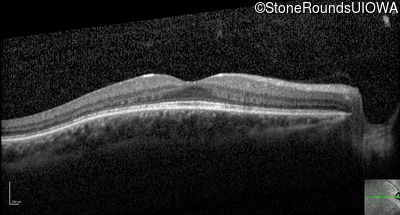

Optical Coherence Tomography - Right - 20/20

Exemplar / OCT Stack